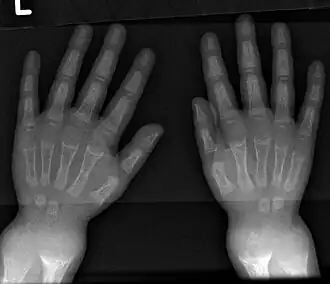

- Radiography typically shows widening of the zones of provisional calcification of the metaphyses secondary to unmineralized osteoid. Cupping, fraying, and splaying of metaphyses typically appear with growth and continued weight bearing.[47] These changes are seen predominantly at sites of rapid growth, including the proximal humerus, distal radius, distal femur, and both the proximal and the distal tibia. Therefore, a skeletal survey for rickets can be accomplished with anteroposterior radiographs of the knees, wrists, and ankles.[47]